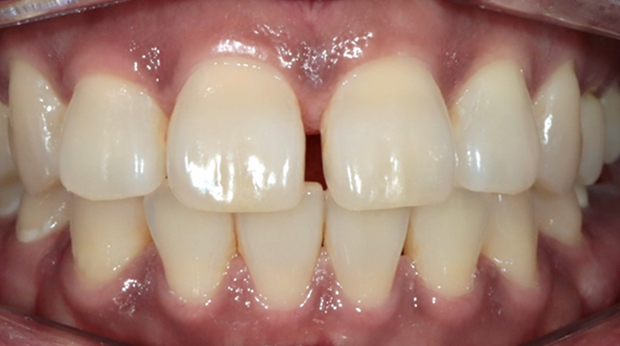

라미네이트